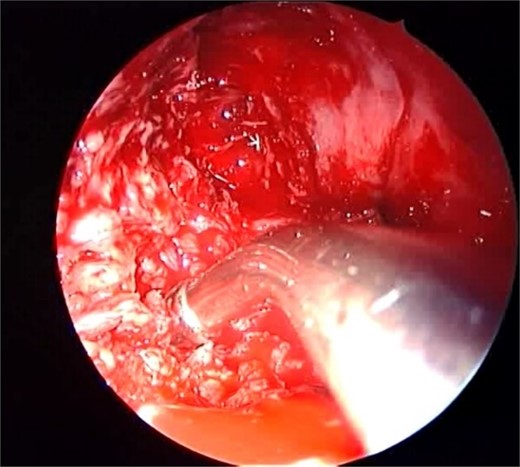

A 12-year-old young girl with relapsing acute myeloid leukemia presented with fever, headache, and left maxillary facial pain. Her symptoms were associated with blood-tinged nasal discharge. Nasal endoscopic examination showed friable ulcerative mucosa of the left middle turbinate and osteo-meatal complex which raised a clinical suspicion of invasive fungal sinusitis. Thus, a contrast-enhanced CT scan (CECT) (Fig. 3) was necessary which showed enhancing left maxillary sinus opacity suggestive of acute invasive fungal sinusitis. The patient underwent urgent endoscopic medial maxillectomy with removal of invasive fungal debris (Fig. 4) along with debridement of left middle turbinate, medial maxillary wall, and orbital floor. A diagnosis of invasive mucormycosis was confirmed by histopathology. The patient was started on aggressive treatment in the form of intravenous and oral antifungal medications. She was regularly followed up for the next 5 years with no evidence of recurrence.

Intra-operative endoscopic maxillary examination (A and B) showing invasive fungal debris.